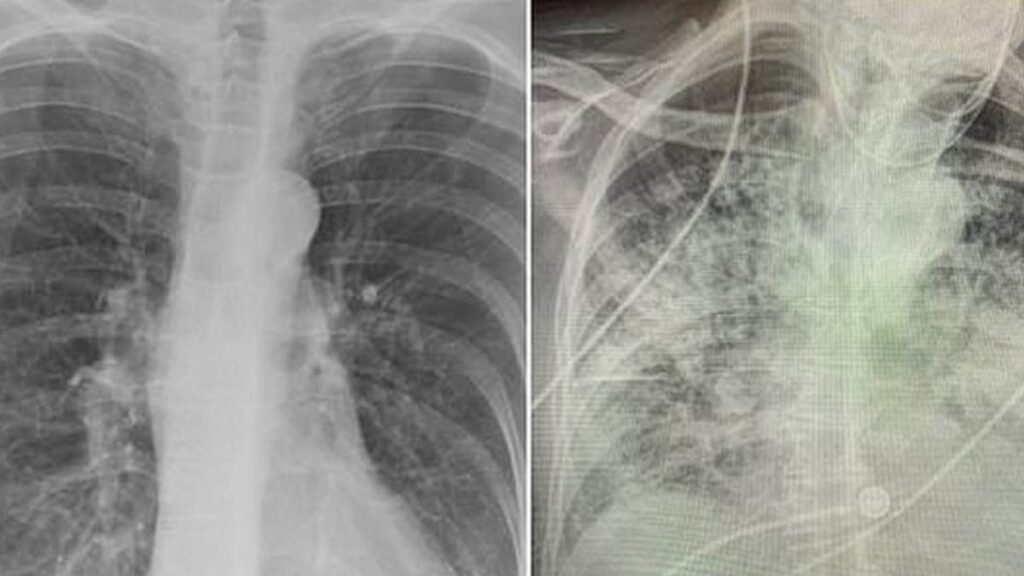

Akciğerler, sigaranın en belirgin etkilerini gösterdiği organdır. Sigara içmek, akciğerlerin görünümünü değiştirerek onları daha koyu ve sert hale getiriyor ve iltihaplanmaya yol açıyor.

Sigarayı bırakan eski sigara içenlerin akciğerleri iyileşmeye başlar. Araştırmalar, sigaranın neden olduğu hasarın tersine çevrilmesinin yanı sıra akciğer hücrelerindeki DNA’da olumlu değişiklikler olduğunu göstermiştir.

Eski sigara içenlerde sağlıklı akciğer hücreleri, sigara içenlere göre dört kat fazladır. Bu hücreler, hava yollarını kaplayan hücreleri yenileyerek kanser riskini azaltmaya yardımcı olur. Sigara içmek, kansere yol açabilecek genetik hatalara yol açar, ancak sigarayı bırakmak bu süreci durdurur ve sağlıklı hücrelerin oluşumunu destekler.